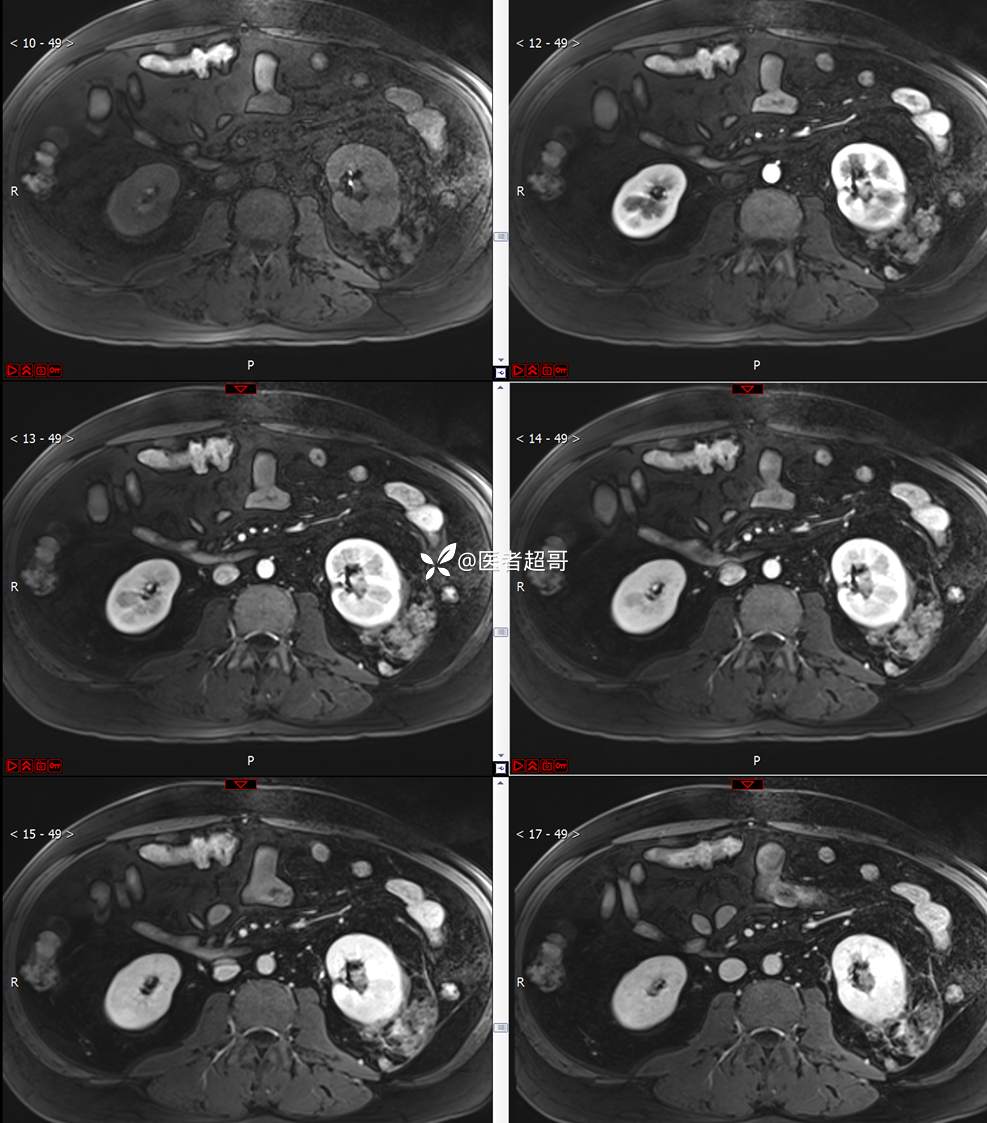

主 诉:查体发现左肾肿物9天。

现病史:患者9天前于附属医院行常规腹部CT检查时,发现左肾占位性病变并肾周脂间隙软组织增多,自述无明显腰腹部不适,无尿频、尿急、尿痛及肉眼血尿,未予特殊治疗,患者近期无头晕头迷,胸闷气急,腹胀腹泻及其他部位明显不适,遂至我院就诊,门诊以“肾肿物”收入院,患者自发病以来,精神可,睡眠饮食可,大便正常,体重无明显减轻。